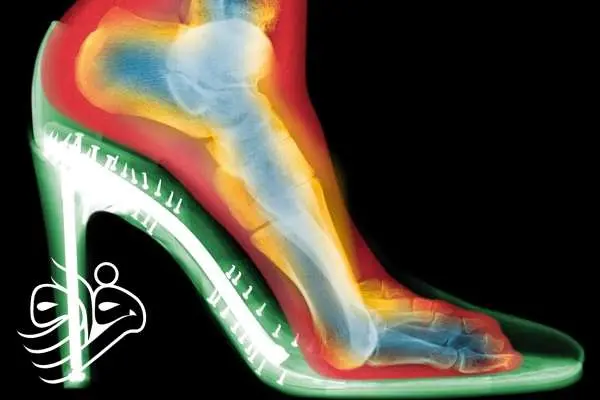

اسکن‌های سه‌بعدی چه نشان دادند؟

گلدبرگ دو اسکن از پای یک فرد تهیه کرد: یکی بدون کفش و دیگری با کفش پاشنه‌بلند. تفاوت‌ها چشمگیر بود:

فشردگی انگشتان :  انگشتان پا در کفش به هم فشرده شده بودند؛

انحراف شست پا (بونیون) :  مفصل انگشت شست به طرف بیرون متمایل شده بود؛

انگشتان چنگالی :  انگشتان کوچک‌تر برای حفظ تعادل، حالتی قفل‌شده و خمیده به خود گرفته بودند.